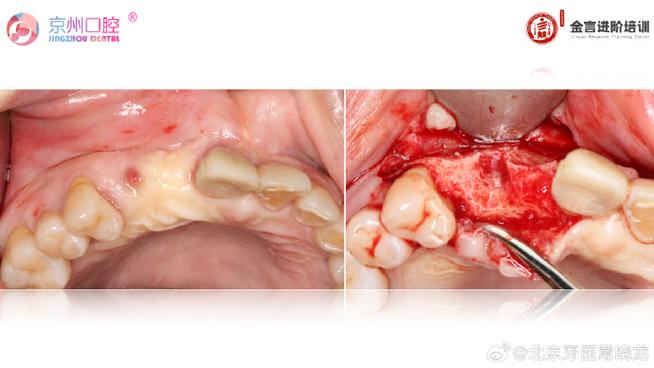

- GTR手术阶段:

- 局麻下进行。

- 翻瓣,彻底清创病变区。

- 根据缺损类型和大小,选择合适的骨移植材料(自体骨、异体骨、骨代用品)和生物屏障膜(可吸收膜如胶原膜、PLGA膜;不可吸收膜如ePTFE膜)。

- 精确放置材料和膜,确保完全覆盖缺损区并超过边缘至少2-3mm。

- 无张力缝合关闭创口,确保膜被完全覆盖。

- 术后严格口腔卫生指导和维护,避免感染和膜暴露。